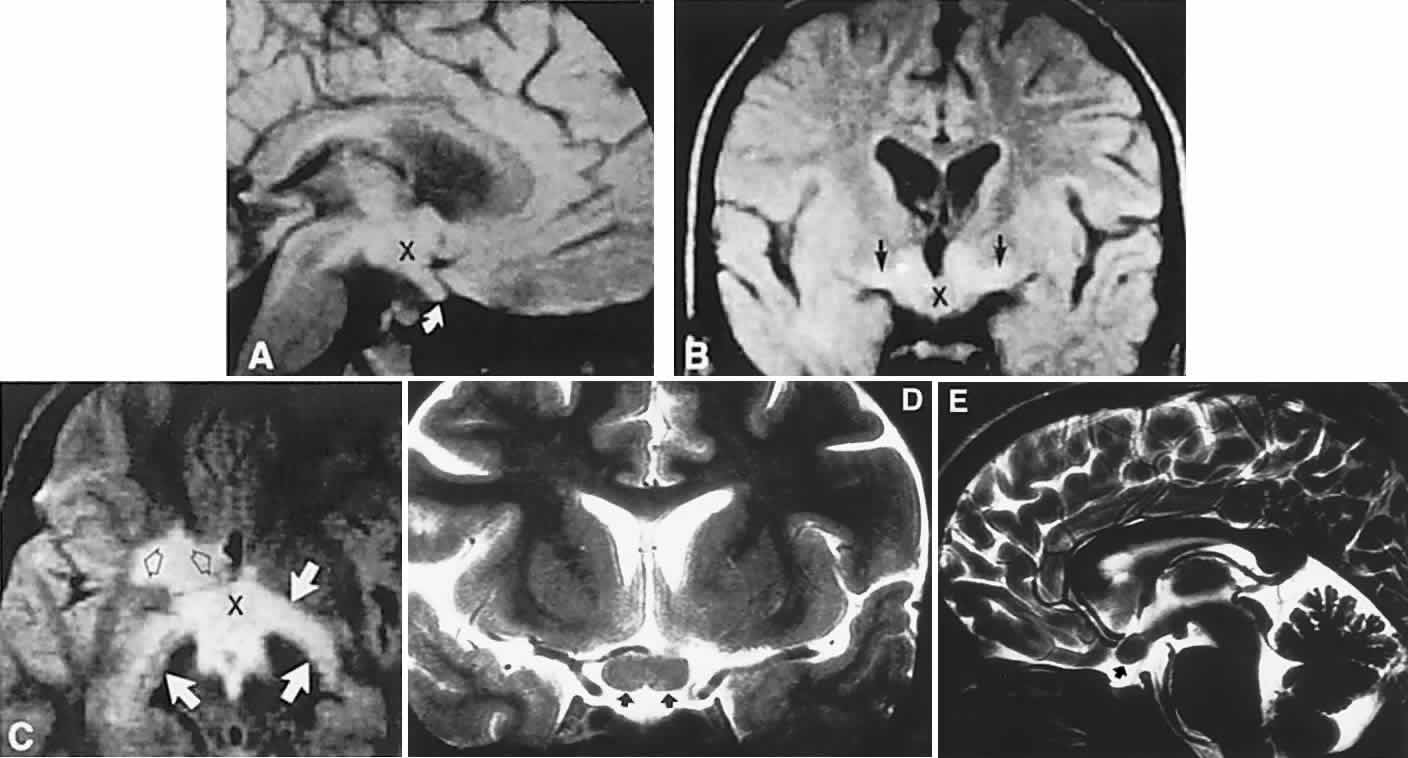

In previous decades, chiasmal interference with optic atrophy, but “normal” plain skull films, was referred to as “Cushing's syndrome of the chiasm,” caused by meningiomas, aneurysms, or other noncalcified suprasellar lesions. The modern neuroimaging techniques of enhanced CT, “bone-window” protocols, and gadolinium-contrasted MRI are now exceedingly sensitive in disclosing meningiomas or other parachiasmal masses (Fig. 4). At present, contrast-enhanced CT or MRI precisely demonstrate extra-axial tumor configuration; CT is superior in disclosing calcification or bone changes, but it is inferior for assessing suprasellar or intrasellar extension, postsurgical changes, and vascular displacement or encasement.76 Whether MRI or even MR angiography obviates standard selective arteriography, especially when surgical intervention is contemplated, is moot.

Fig. 4. Magnetic resonance imaging of a suprasellar meningioma (TR, 600 milliseconds; TE, 20 milliseconds). A. Coronal section of a large meningioma (large arrows), isodense to brain. B. Sagittal section. Note the normal sella and pituitary gland (p). Sagittal (C) and coronal (D) sections of a planum meningioma, extending into the sella. Note the upward deflection of the chiasm (arrow in C) and extension to the cavernous sinus (arrows in D).